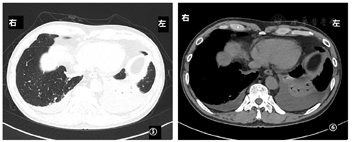

因患者拒绝有创检查,遂先予抗感染(左氧氟沙星0.5 qd静脉滴注)7 d。至2020年12月8日复查胸部CT(图5,图6)提示病情进展,双肺多发实性小结节影较前增多,两下肺渗出及胸腔积液增多。

经3个月余治疗后患者胸痛、气促症状缓解,一般状态好,无明显不良反应。当地医院2021年4月6日复查胸部CT提示胸腔积液已吸收,纵隔淋巴结较前明显缩小,目前继续使用泽布替尼(剂量同前),已随访9个月余,随访继续中。